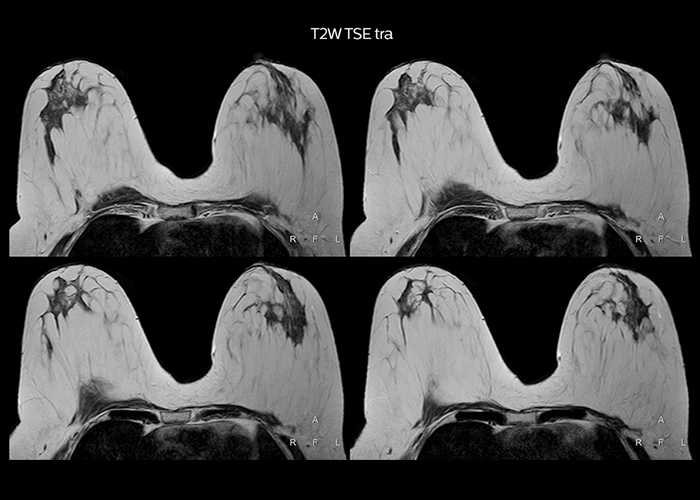

“To avoid coil changes we plan examinations of similar anatomies back to back, such as head and spine. Multiva helps us here a lot because coils don’t need to be changed frequently. Moreover, thanks to parallel imaging technology and 16-channel HeadSpineTorso and 8-channel MSK coils we are able to achieve excellent image quality. In this way Multiva helped us to increase both image quality and productivity.”

“Most important, Multiva satisfies our clinical imaging needs very well,” says Mr. Tuna. “Many features of Multiva have become similar to the Ingenia system. Even in more complex imaging such as abdominal and cardiac, the image quality and performance of Multiva is better than we expected. General surgeons and physicians from our hospital’s internal medicine department prefer to refer to us because of this.”